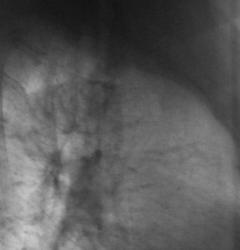

Вот прошлогодняя флюорограмма.

Вот посему, мы и предположили, наличие, как ранее называли, перибронхиального рака. Правда сейчас, он по всей видимости, отнесен к одному из видов БАР.